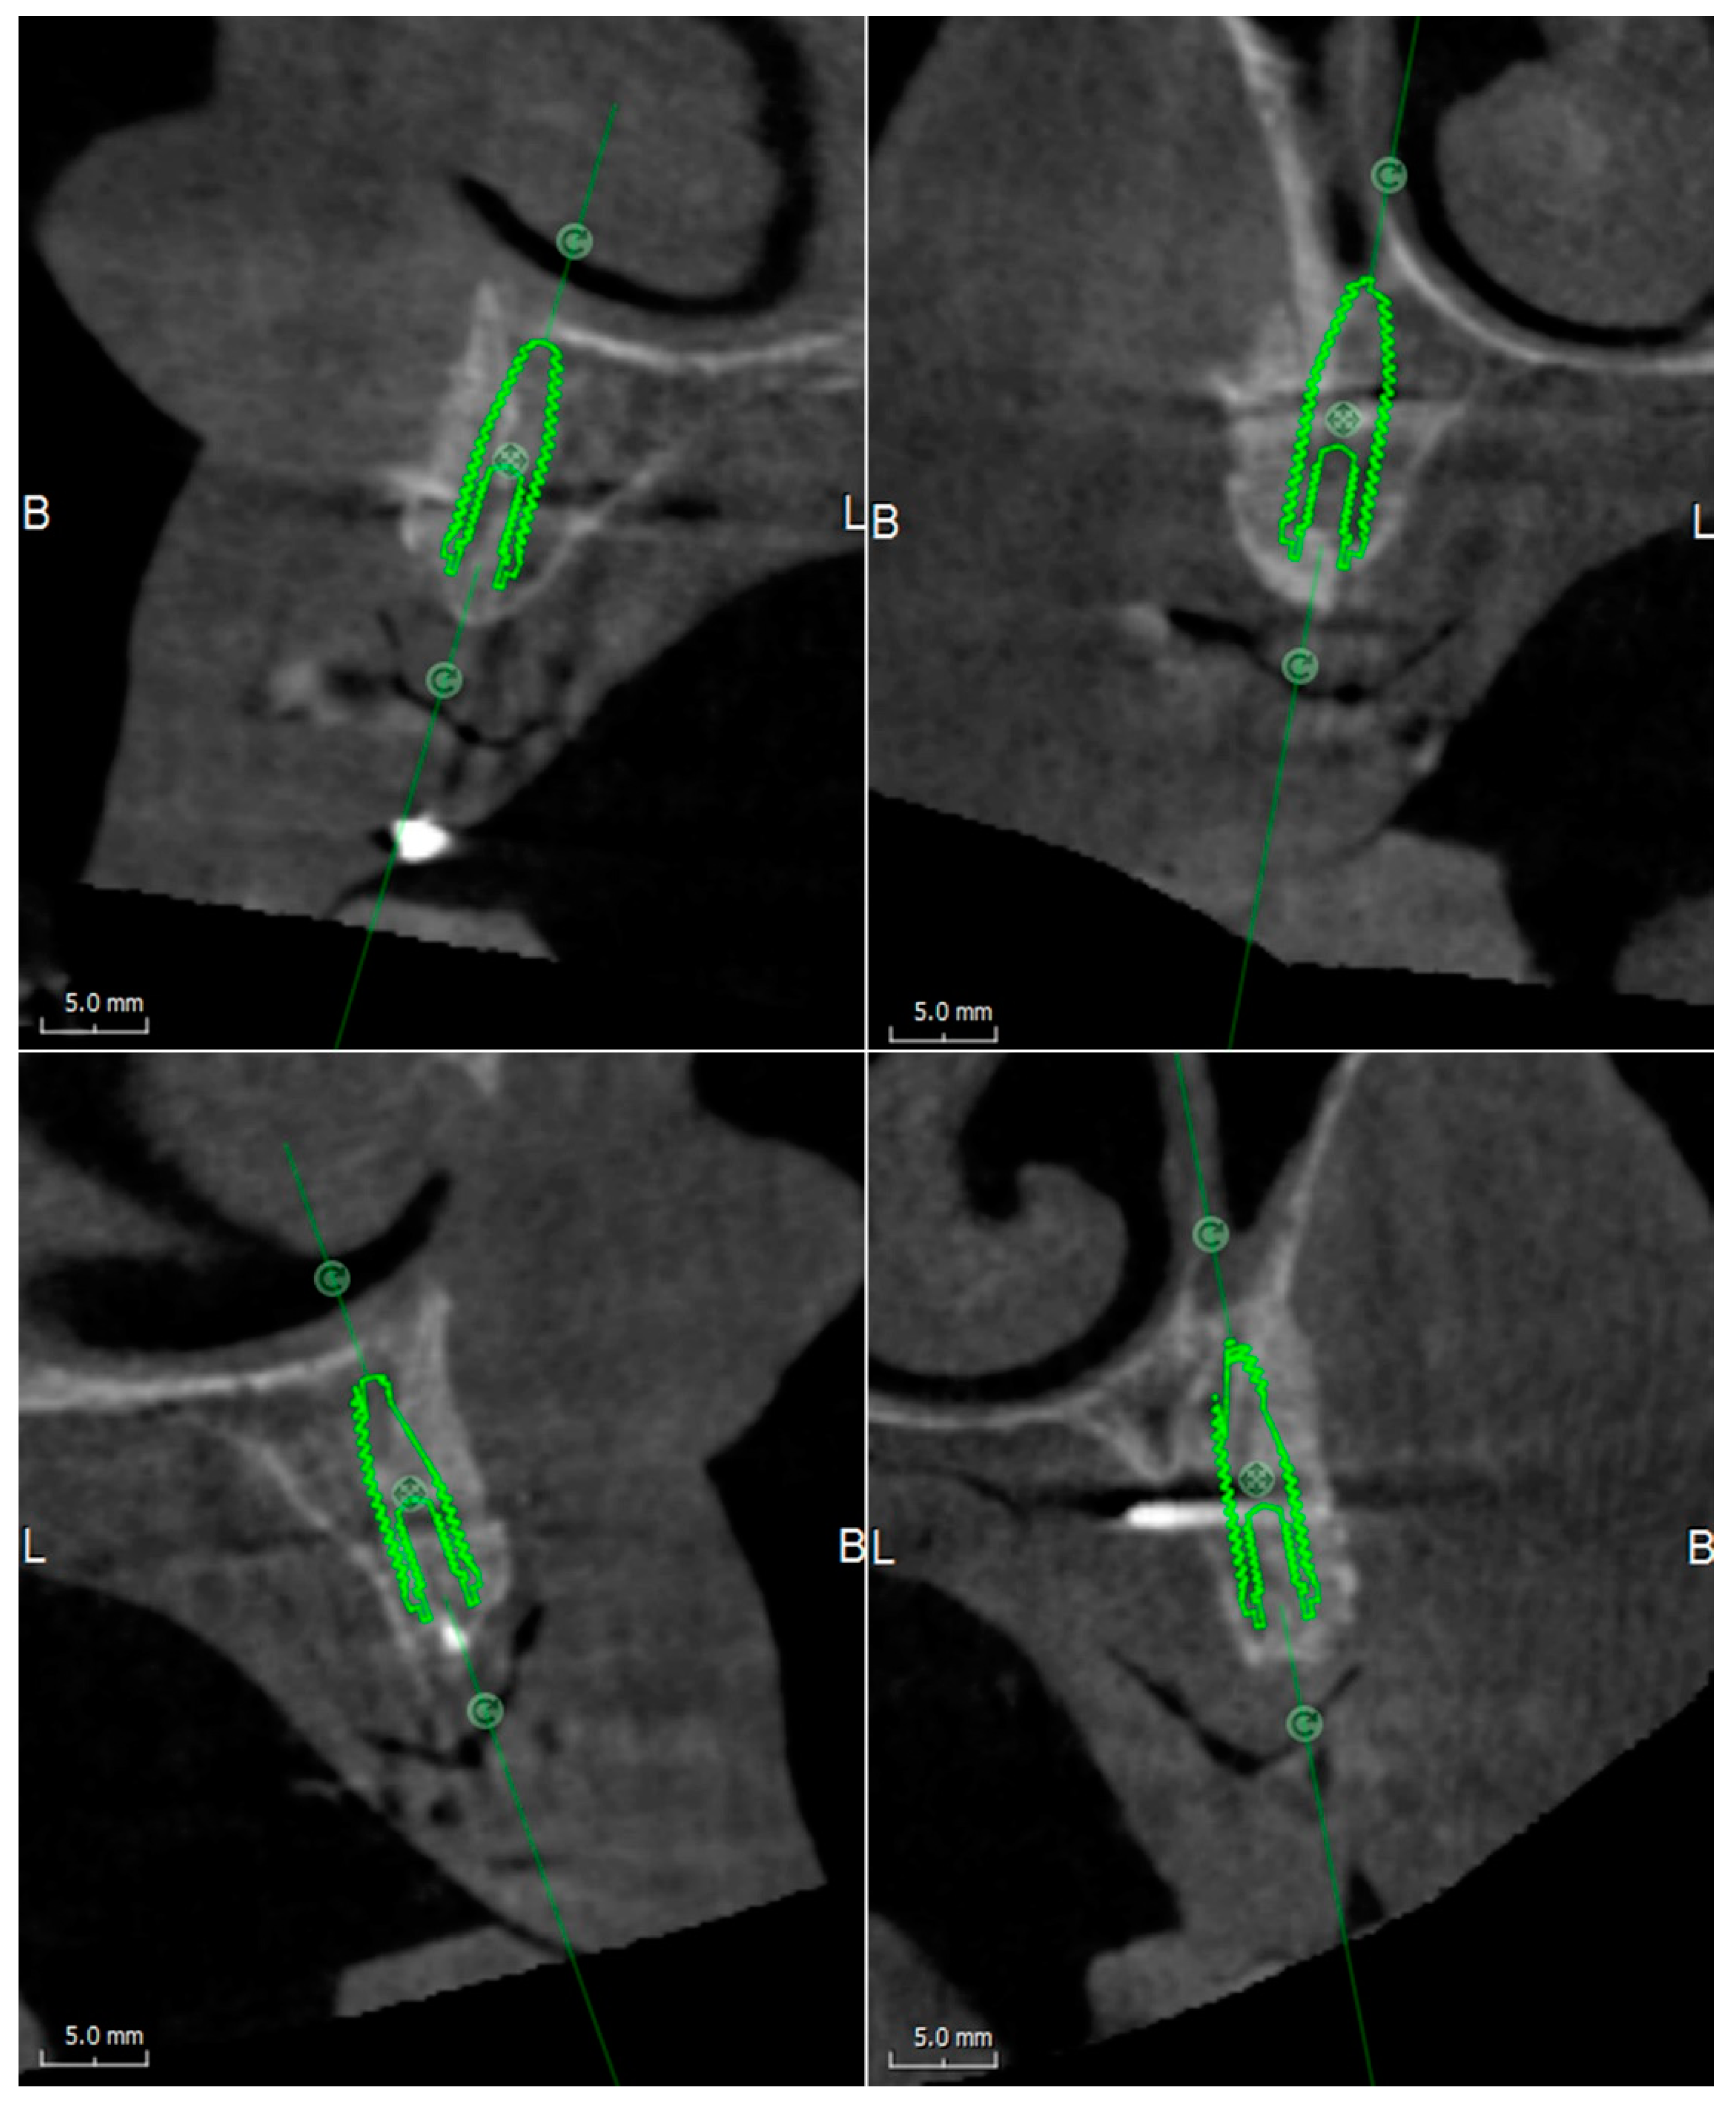

The CBCT performed at six months after the first intervention of the bone reconstruction showed the integration between the graft and the recipient site and a three-dimensional volume of the alveolar ridge adequate for the placement of the implants (Figure 5).

Figure 5. CBCT, performed at six months after reconstructive surgery, shows the integration of grafted blocks at planned implant sites.